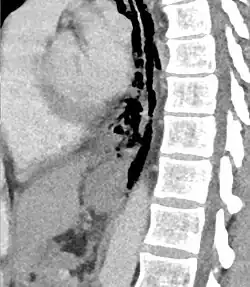

Axial CT image through the upper chest showing extraluminal air (Pneumomediastinum) surrounding the trachea and esophagus | |

The diagnosis of Boerhaave syndrome is suggested on the plain chest radiography and confirmed by chest CT scan. The initial plain chest radiograph is almost always abnormal in patients with Boerhaave syndrome and usually reveals mediastinal or free peritoneal air as the initial radiologic manifestation. With cervical esophageal perforations, plain films of the neck show air in the soft tissues of the prevertebral space.

Hours to days later, pleural effusion(s) with or without pneumothorax, widened mediastinum, and subcutaneous emphysema is typically seen. CT scan may show esophageal wall edema and thickening, extraesophageal air, periesophageal fluid with or without gas bubbles, mediastinal widening, and air and fluid in the pleural spaces, retroperitoneum or lesser sac.